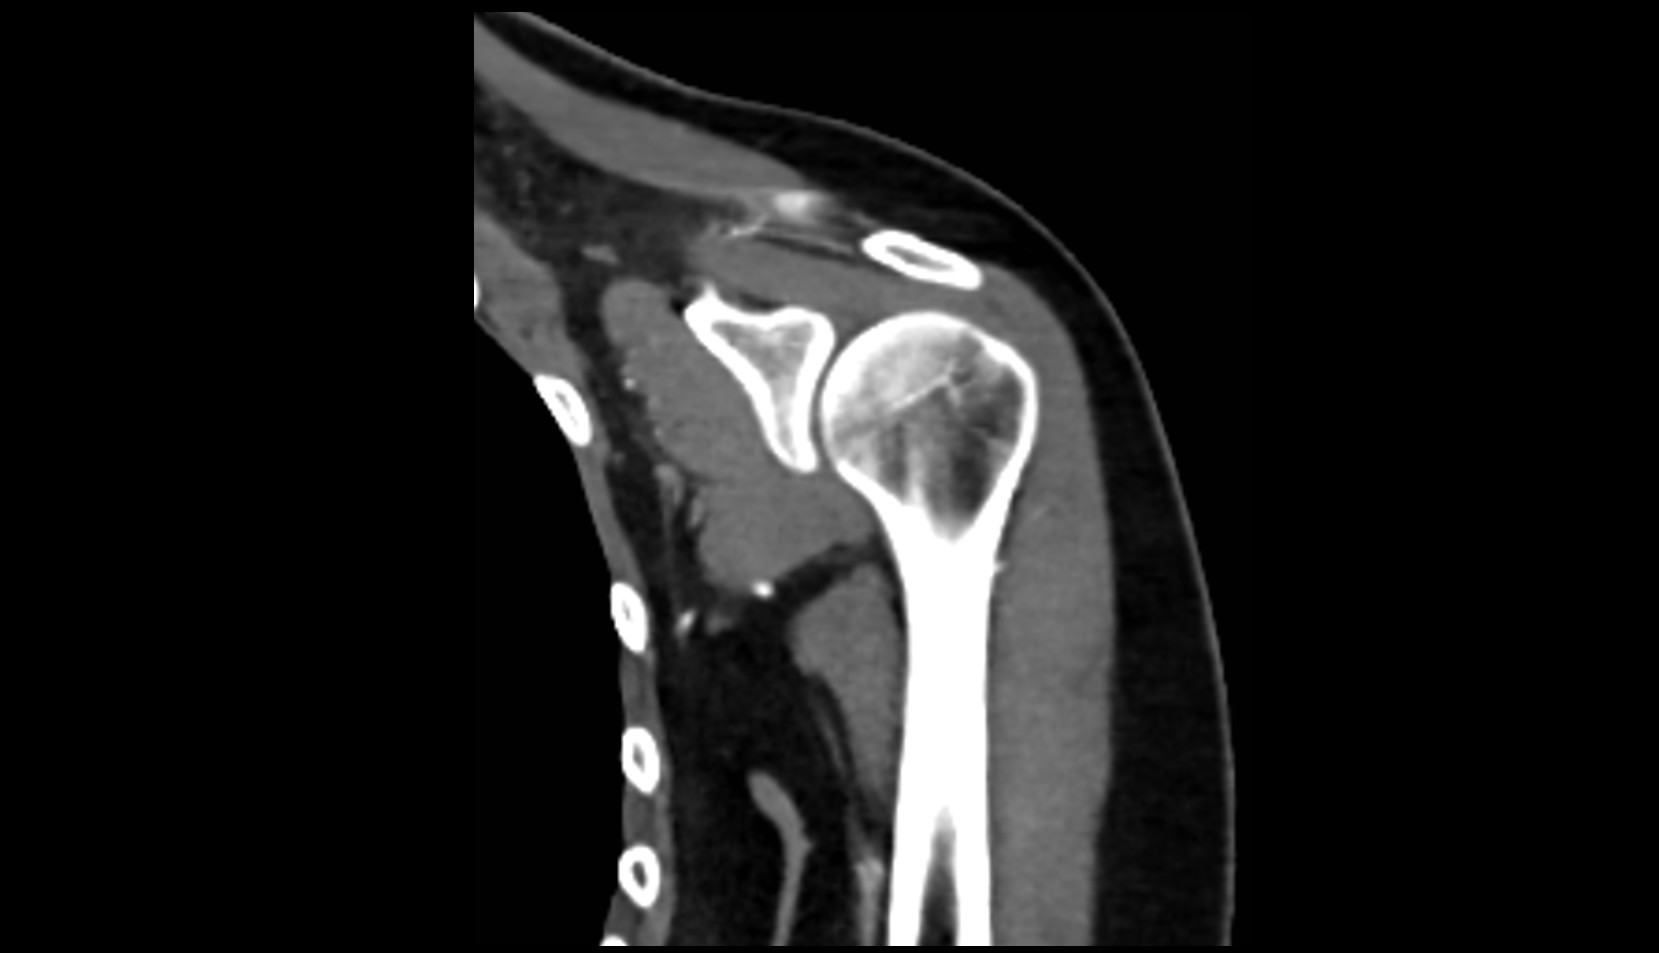

- Glenoid fossa

- Glenoid process of scapula

- Spine of scapula

- Acromion process of scapula

- Coracoid process of scapula

- Scapular body

- supraspinous fossa of scapula

- Subscapular fossa

- Neck of scapula

- Humerus

- Head of humerus